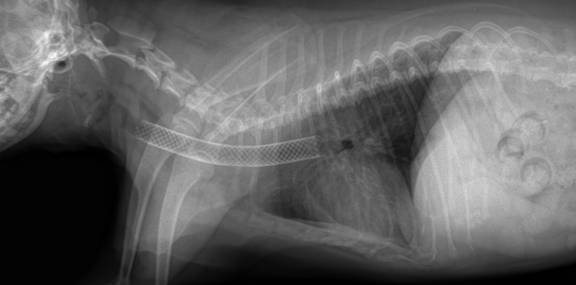

Рентгеновский снимок, трахея до стентирования:

И после стентирования: